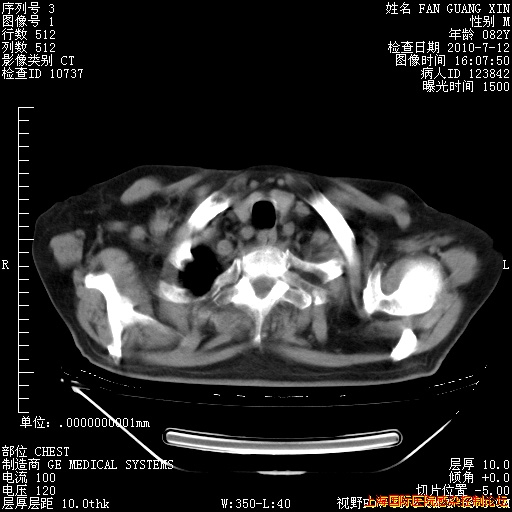

今天复查CT

今天CT

整整相隔30天的肺部CT好像有所好转啊。甲强龙减量第3天,需要观察体温。